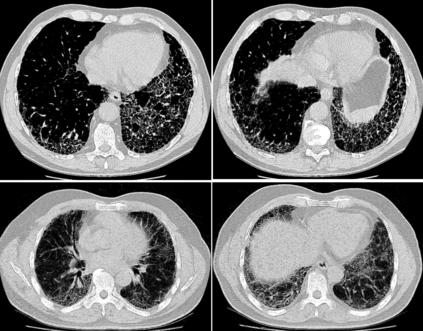

Pulmonary fibrosis is a devastating chronic lung disease that causes irreparable lung tissue scarring and damage, resulting in progressive loss in lung capacity and has no known cure. A critical step in the treatment and management of pulmonary fibrosis is the assessment of lung function decline, with computed tomography (CT) imaging being a particularly effective method for determining the extent of lung damage caused by pulmonary fibrosis. Motivated by this, we introduce Fibrosis-Net, a deep convolutional neural network design tailored for the prediction of pulmonary fibrosis progression from chest CT images. More specifically, machine-driven design exploration was leveraged to determine a strong architectural design for CT lung analysis, upon which we build a customized network design tailored for predicting forced vital capacity (FVC) based on a patient's CT scan, initial spirometry measurement, and clinical metadata. Finally, we leverage an explainability-driven performance validation strategy to study the decision-making behaviour of Fibrosis-Net as to verify that predictions are based on relevant visual indicators in CT images. Experiments using a patient cohort from the OSIC Pulmonary Fibrosis Progression Challenge showed that the proposed Fibrosis-Net is able to achieve a significantly higher modified Laplace Log Likelihood score than the winning solutions on the challenge. Furthermore, explainability-driven performance validation demonstrated that the proposed Fibrosis-Net exhibits correct decision-making behaviour by leveraging clinically-relevant visual indicators in CT images when making predictions on pulmonary fibrosis progress. While Fibrosis-Net is not yet a production-ready clinical assessment solution, we hope that its release in open source manner will encourage researchers, clinicians, and citizen data scientists alike to leverage and build upon it.